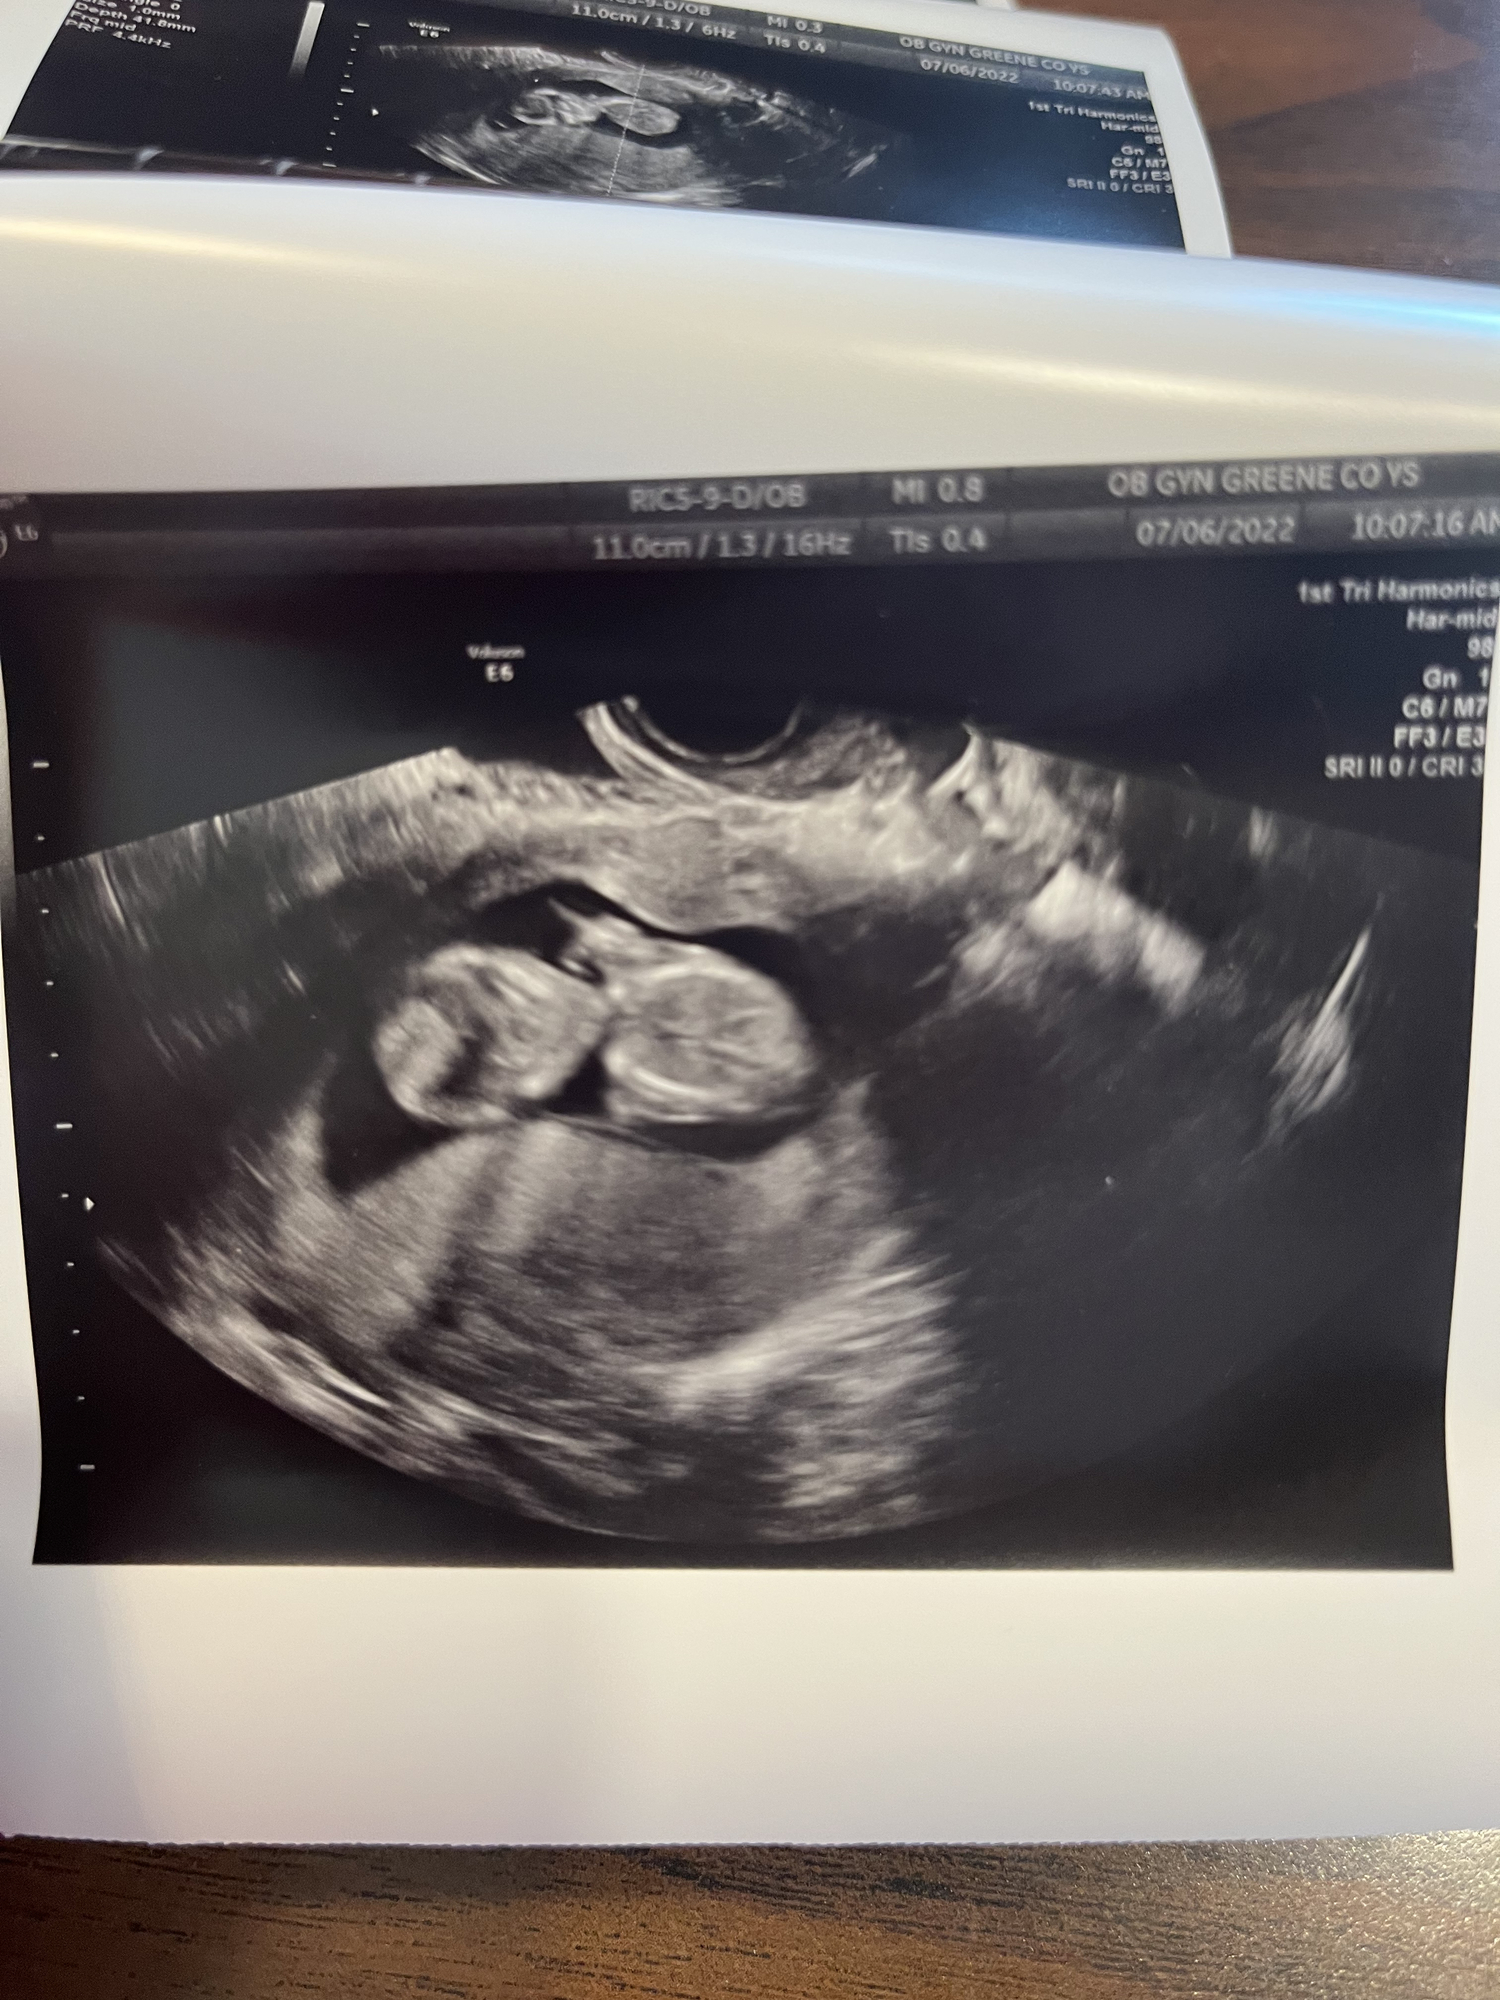

Ramzi/nub?

Anyone have any guesses?

Ramzi and nub are about 50% accurate, and this picture can’t be used for either of them.

I'm 100% right that its a 50% guess of girl and 50% guess boy

75% chance it's a human baby